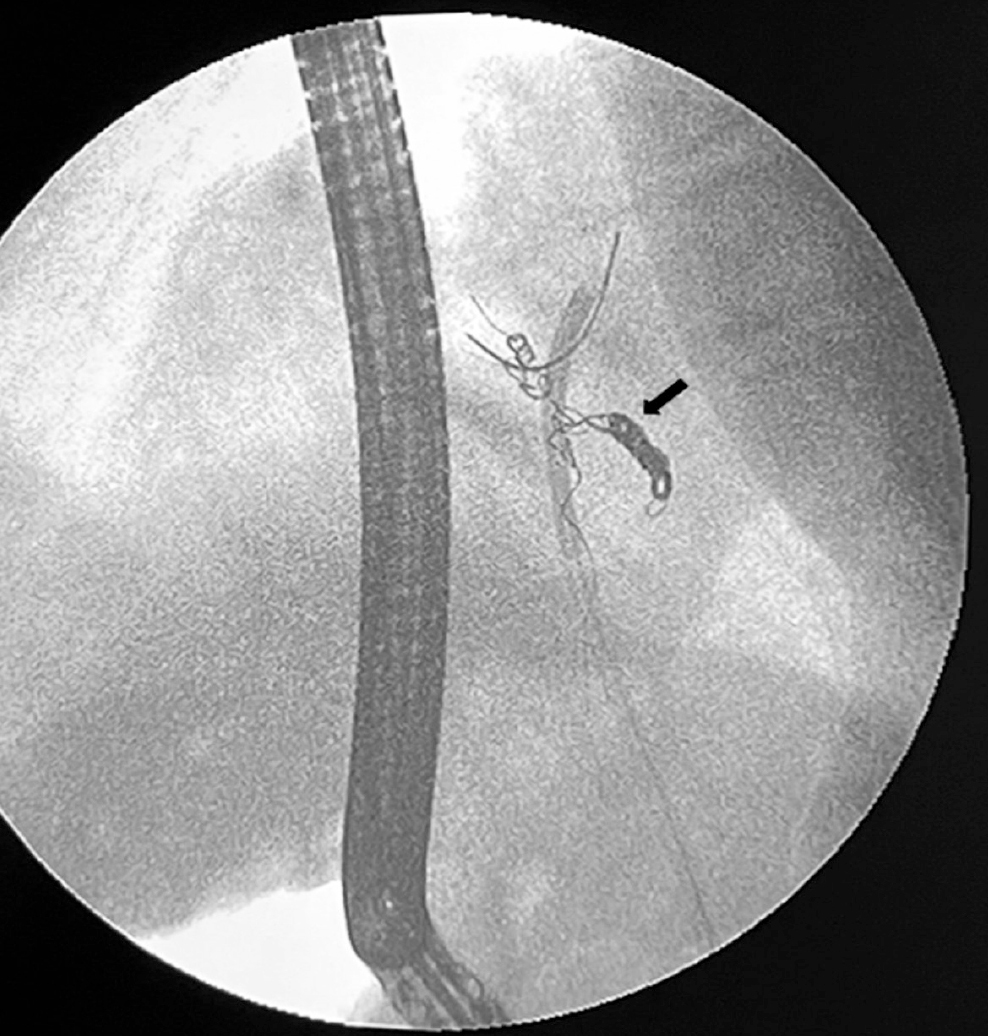

Extracción endoscópica de coils migrados a la vía biliar: reporte de casos y revisión de la literatura

La embolización es un procedimiento que se realiza de manera frecuente para el manejo de patologías vasculares y no vasculares, la potencial migración a la vía biliar de los coils utilizados se ha descrito en la literatura y la presentación clínica suele ser similar a la obstrucción de la vía biliar por coledocolitiasis. Se presentan dos casos de coils migrados a la vía biliar después de una embolización arterial y su posterior extracción por vía endoscópica. Este manejo es ideal; sin embargo, la técnica a utilizar depende de las condiciones clínicas y la anatomía de cada paciente.